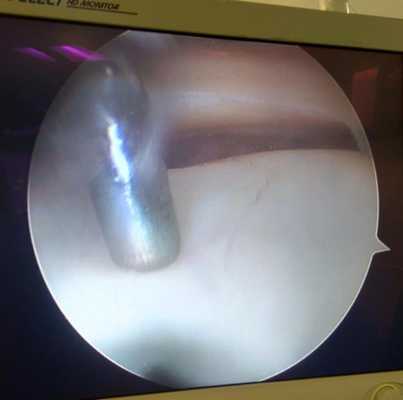

Свободное внутрисуставное тело коленного сустава, состоящее из отслоенного участка хряща внутреннего мыщелка бедра на фоне его постоянной травматизации фрагментов разорванногомениска.

Свободное внутрисуставное тело коленного сустава после удаления, состоящее из отслоенного участка хряща внутреннего мыщелка бедра и причина отслойки - дегенеративно изменённый задний рог внутреннего мениска.